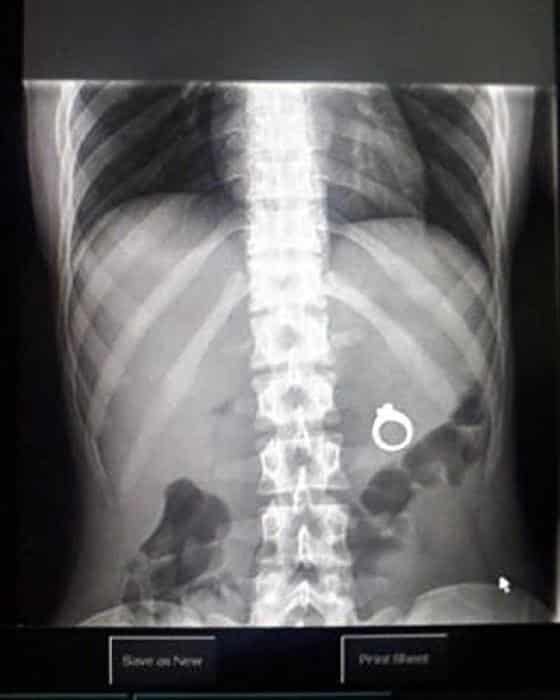

33 radiographies qui prouvent que les gens font des choses douteuses avec leur corps !